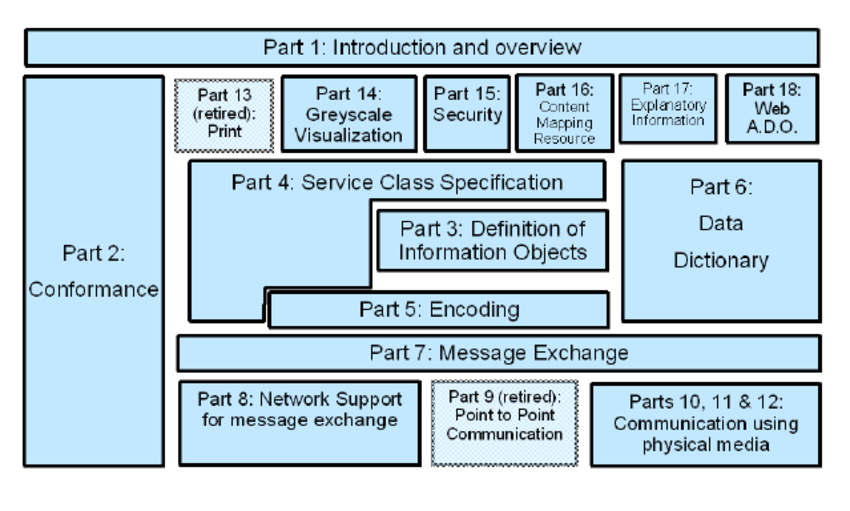

Questo standard, applicato alla codifica dei file, non è nient’altro che un metodo per incapsulare i dati e per definire come questi debbano essere codificati o interpretati, ma non definisce alcun nuovo algoritmo di compressione.

Inoltre, questo metodo si occupa della visualizzazione delle immagini, ma anche della gestione dei dati ad esse relative, definendo quali operazioni possono essere eseguite e su quali oggetti.